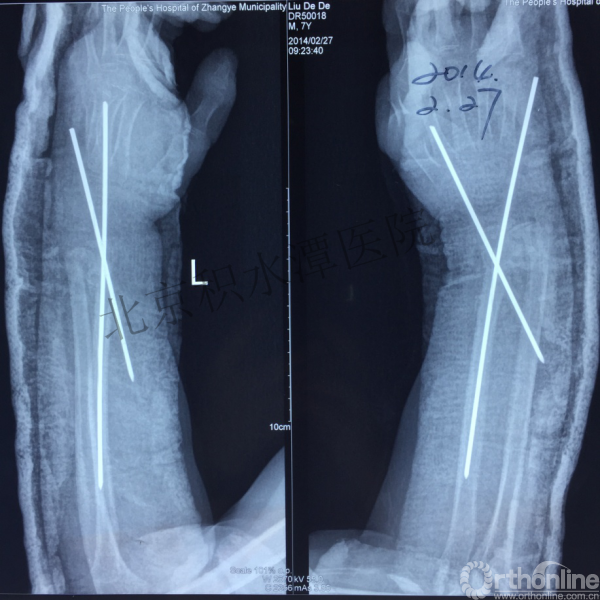

病例分享一

男孩 、5岁,初次骨折于2007年7月。

术后2年→再骨折→再次手术

钢板固定后一年

取板后再骨折→TEN

TEN取出后2个月

闭合复位再固定加尾帽

又过了4年!时间来到2015年

一年以后顺利愈合,实则危机四伏

数月后再骨折!牵引!

髋人字支具

外固定架术后一年

整整11年!是否治疗终结?

病人的付出?医生当反思!